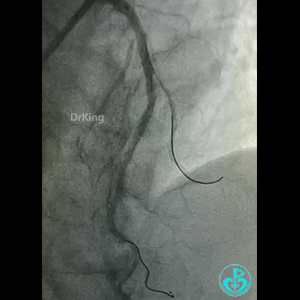

导丝怎么扩真怪!急性心梗前降支导丝通过顺利,球囊扩张后导丝移位很多!不在原来的血管腔!_https://www.jmylbn.com_新闻资讯_第4张

前降支也后扩了。

微导管造影,后面还是放了支架。